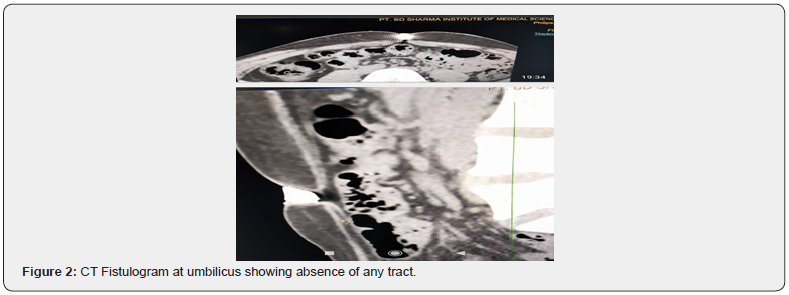

An 18-year-old female, a known case of Koch’s chest and was treated completely for it 12 years back. She had history of passage of two worms with per rectally ten years back. Now she presented with intermittent pain abdomen for last one year for which was being treated with oral and intravenous analgesics by local practitioners but was never fully investigated for the same. She had single episode of small amount of hematemesis two months back which was symptomatically treated as upper Gastrointestinal endoscopy done at that time was normal. After few days of this hematemesis episode, she developed passage of frothy fluid with feculent smell from umbilicus and she has to change her dress three-four times per day due to repeated wetting of her clothes. Subsequently her pain abdomen increased and was mainly Periumblical and associated with anorexia followed by passage of worms from umbilicus along with itching, fever for last six weeks. She had one more episode of upper gastrointestinal bleed at home and upper gastrointestinal endoscopy done after a gap of one week when she was admitted in our hospital was normal. She also gave history of irregular menstrual cycles, gynecological evaluation for which was normal, and it was attributed to anemia. On physical examination, the patient was conscious, co-operative, in discomfort, febrile and anemic. The systemic examination including chest, cardiovascular, central nervous system, ophthalmological and dermatological was normal. The complete haemogram revealed hemoglobin of 9.6 g/dL, white blood cell counts 13,200/L, microcytic hypochromic anemia with no malaria parasite. The renal & liver function test, blood sugar, serum amylase & electrolytes, serum vitamin B12, D3, folic acid levels, urine & blood culture, thyroid & complete lipid profile, viral screen including hepatitis B, C, HIV were all essentially normal. The electrocardiogram and chest x-ray were normal. The stool examination on wet mount confirmed presence of ova of hookworm. The live worms which were coming out of umbilicus on microscopic examination were confirmed as hookworm. The ultra-sonogram and computed tomography scan of abdomen was normal. The computed tomography Fistulogram from umbilicus was unable to show any tract between umbilicus and intestine or any other part which could have proven to be passage for worms from umbilicus. The patient was treated with mebendazole 100mg twice daily for five days, but worms kept on coming through umbilicus, though their number reduced from twenty to twenty-five per day to five to seven per day. Then patient was put on albendazole & ivermectin combination which led to further decrease in number of worms coming from umbilicus to one to two per day, followed by decrease in size of worms and ultimately after a gap of one week, no worms were seen coming out of umbilicus. The fever subsided but pain abdomen was persistent (Figure 1,2).

Hookworm infection is endemic especially in tropical underdeveloped countries and one billion people are infected with it in the world [3,4]. It is mainly seen in rural areas, especially in children & young women and is important cause of iron deficiency anemia. The adult worm resides in small intestine mucosa, thus leading to recurrent and persistent small hemorrhages and if ulcer formation is there, then it can cause upper gastrointestinal bleed, as it occurred in our case. The normal endoscopy may have been due to delay and use of proton pump inhibitors. These multiple small and large hemorrhages lead to iron deficiency anemia. The larvae usually enter through the skin, then migrates through the circulatory system, causing the pulmonary cycle, Löeffler’s syndrome, pulmonary edema, alveolar lysis, fever, bronchitis and pneumonia. The filariform larvae can gain entry into body by ingestion of infected water or vegetables and by breastfeeding [5,6]. The disease severity depends on the parasite load, the nutritional and immunological status of the host. The presentation is with pain abdomen, generalized weakness, itching, anemia, hypoprotenemia, fever and in some cases with upper gastrointestinal bleed. Our case also presented with pain abdomen, fever, anemia, anorexia and upper gastrointestinal bleed which is consistent with documented literature. The history of passage of feculent material from umbilicus was suggestive of tract formed by worms between bowel and umbilicus but it being very small may have not been seen on Computed tomography fistulogram through umbilicus. The larvae migrate through circulatory system and can reach various organs of body. The adult worms have been reported in literature to come out through natural orifices like oral cavity, anal canal, nostrils and umbilicus but this is probably first case in world where multiple live worms have been reported to be exiting through umbilicus for many days.